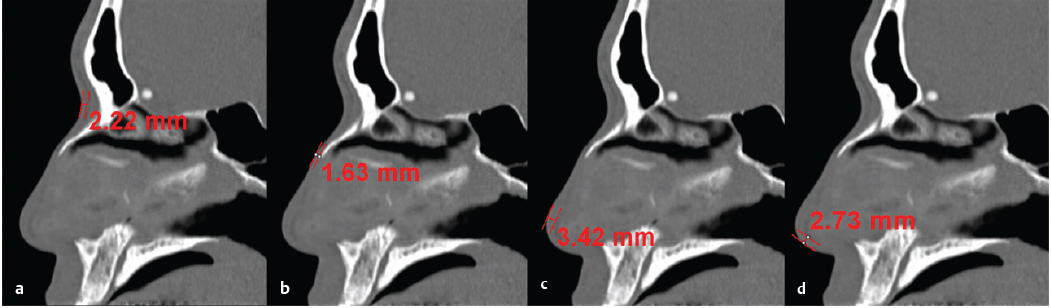

East Asia encompasses China, Korea, Taiwan, and Japan. Also, there are many Chinese descendants in Southeast Asian countries including the Philippines, Thailand, Malaysia, and Vietnam. The typical East Asian nose tends to have thicker nasal skin than Caucasian noses, with abundant subcutaneous soft tissue. In author’s research using computed tomography (CT) scans on the thickness of the nose in Koreans, the mean nasal skin thickness was 3.3 mm for nasion, 2.4 mm for rhinion, 2.9 mm for nasal tip, and 2.3 mm for columella ( Fig. 41.1 ). In the author’s study, thick skin at the nasal tip and columella was associated with poor surgical outcomes, suggesting that regional skin thickness is an important prognostic factor for tip surgery success. 1 The tip of the East Asian nose is usually low and the lower lateral cartilages are small and weak. The nasal bones are poorly developed and thick, thus manifesting low radix. The average nasal length to nasal tip projection to dorsal height to radix height ratio of the Caucasian nose has been shown to be 2:1:1:0.75. 2 However, in the author’s study, young Koreans had a nasal length to nasal tip projection to dorsal height to radix height ratio of 2:0.97:0.61:0.28. 2 These data indicate that East Asians had lower dorsal and radix heights. It was also found that East Asians have a more acute nasolabial angle than Caucasians, but a similar nasofrontal angle. The septal cartilage is thin and small. Therefore, the size and the quantity of harvestable septal cartilage may be inadequate for complete rhinoplasty procedures, indicating the higher possibility of harvesting grafts from other sites. 3